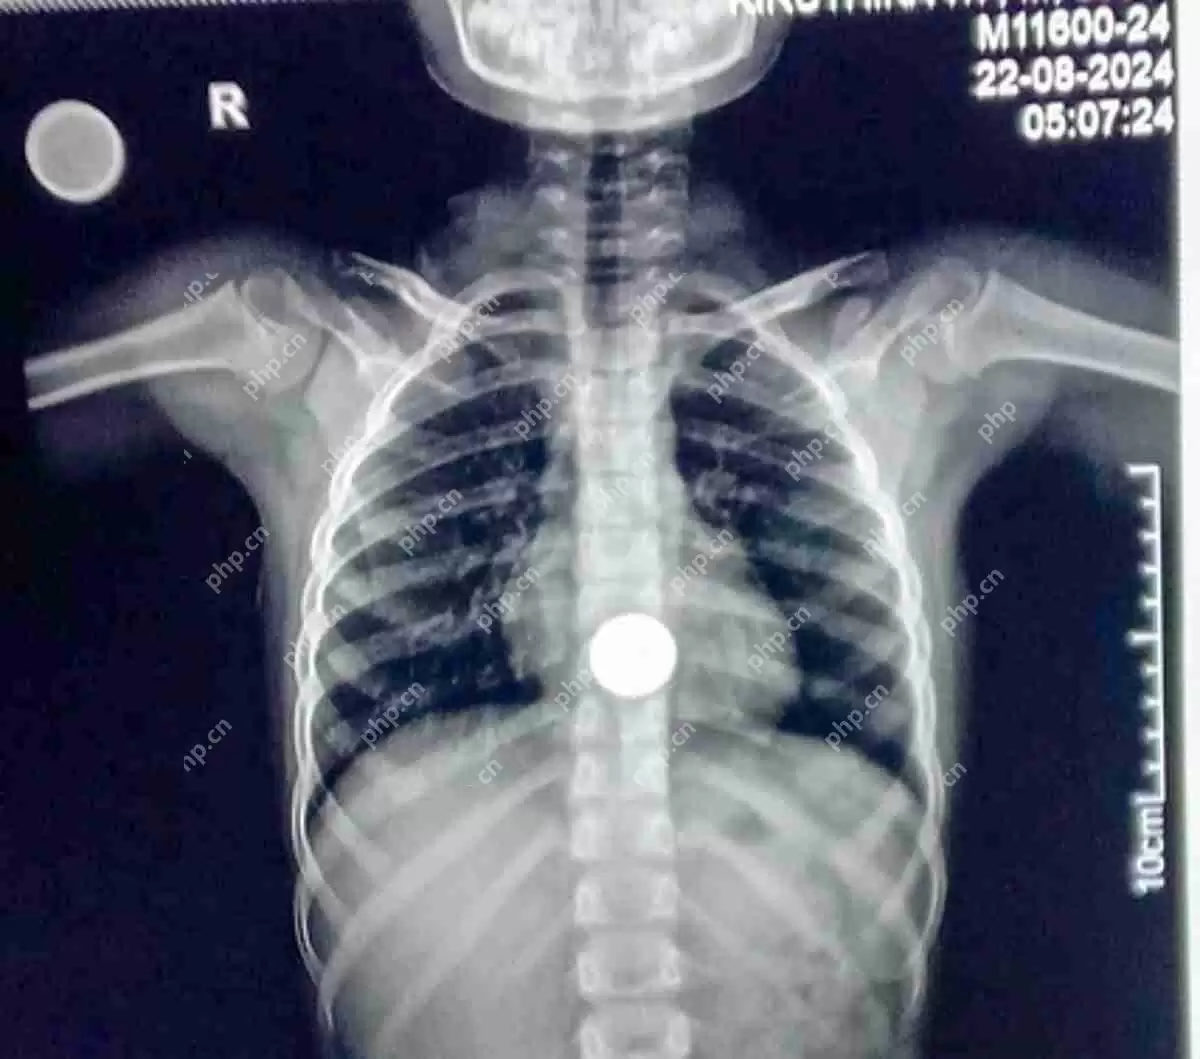

医生紧急手术:从7岁女孩食道取出5卢比硬币

周日,蒂鲁帕塔尔政府医院的医生成功地从七岁女孩坎尼什里的食道中取出了一枚5卢比的硬币。事情发生在周五,坎尼什里不小心吞下了亲戚送给她的这枚硬币。

同时,Deepanand博士在与TNIE的交谈中表示,由于他在附近,且情况紧急,他很快就处理了这件事。他还提到,从食道中取出异物在医院中是相当常见的程序。他解释说:“通常,这些物体会进入食道或胃。如果它们进入气管,情况将变得非常严重。”